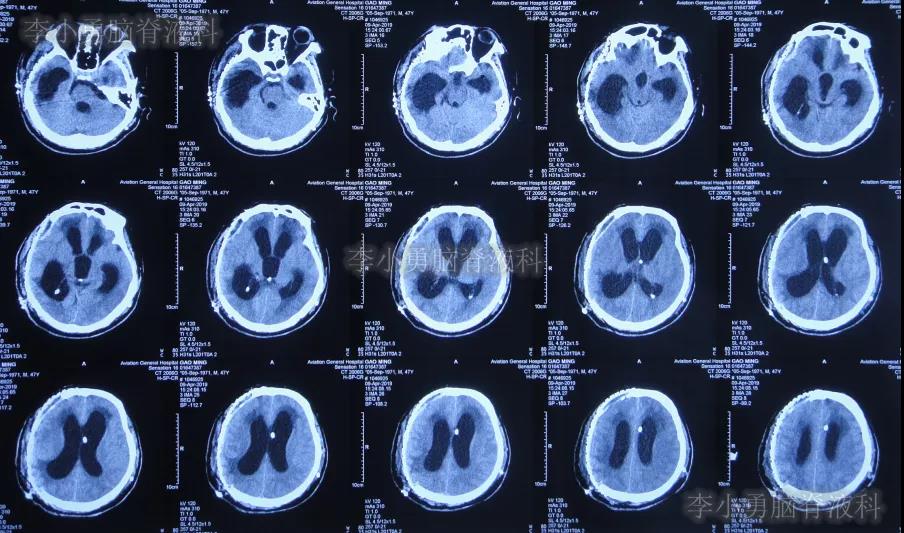

2019年4月2日(第4家医院治疗192天即脑室腹壁外引流术后176天),按计划进行钛网颅骨修补术,术后当天查头颅CT示颅骨修补术后(图-3)。

图-3:2019年4月2日头颅CT

颅骨修补术后7天即2019年4月9日,查头颅CT头颅示颅骨修补术后,仍脑积水(图-4)。

图-4:2019年4月9日头颅CT

颅骨修补术后35天即2019年5月7日(第4家医院治疗227天即脑室腹壁外引流术后211天)),查头颅CT仍脑室扩张(图-5),且引流出的脑脊液有絮状物。

图-5:2019年5月7日头颅CT

第4家医院治疗257天(8个半月),治疗期间患者曾发作癫痫数次,给予药物控制,引流管也曾更换,虽无发热但意识改善不明显,2019年6月6日查头颅CT示脑室仍大(图-6)。

图-6:2019年6月6日头颅CT

第4家医院治疗312天(10个月),意识仍无明显改善,查头颅CT(图-7)后仍脑室扩张,患者出院转回当地的新疆鄯善县某医院。

图-7:2019年7月31日头颅CT